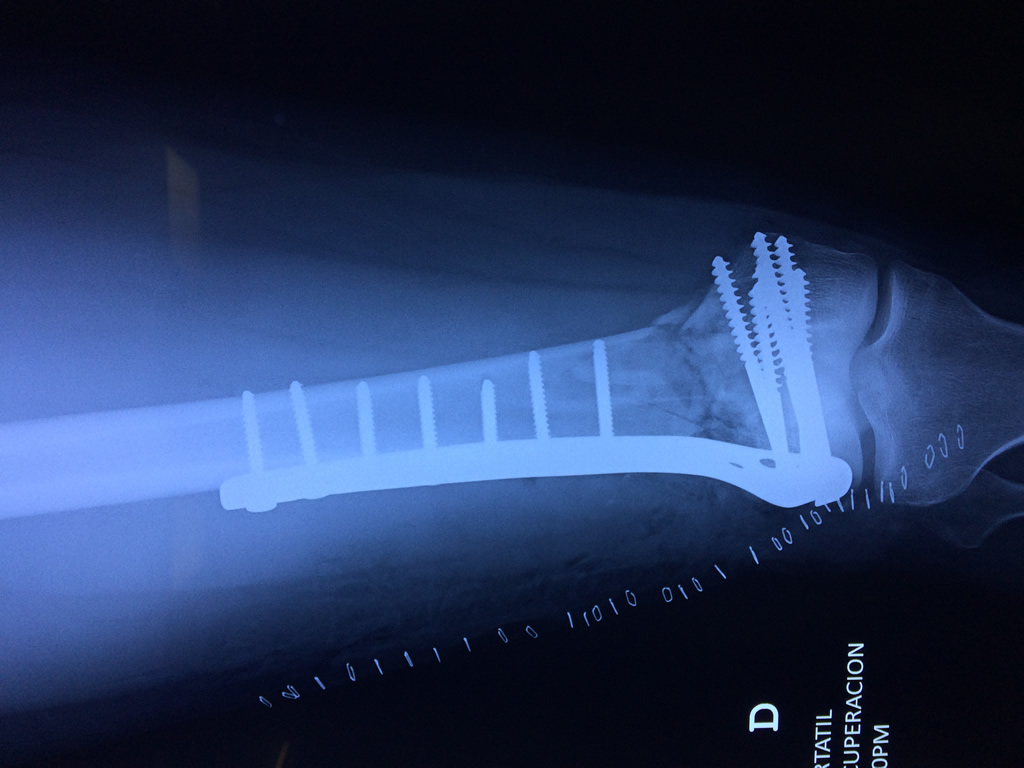

Cirugía de Fémur - Fémur

El fémur es el hueso del muslo, el segundo segmento del miembro inferior. Es el hueso más largo, fuerte y voluminoso del cuerpo humano.